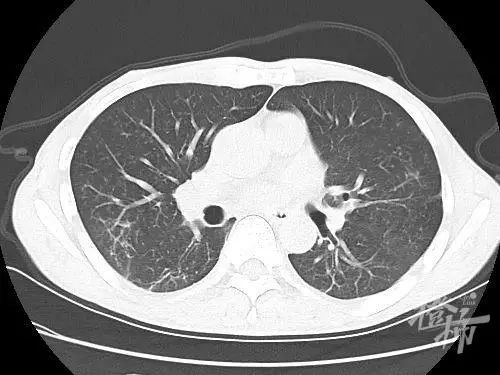

(CT复查显示肺部已基本正常)

在朱侠凯和九龙县人民医院医护团队的精心治疗和护理下,李先生在11月5日撤离呼吸机,成功脱机拔管。

11月12日,李先生平安出院,并写下了文章开头的感谢信。